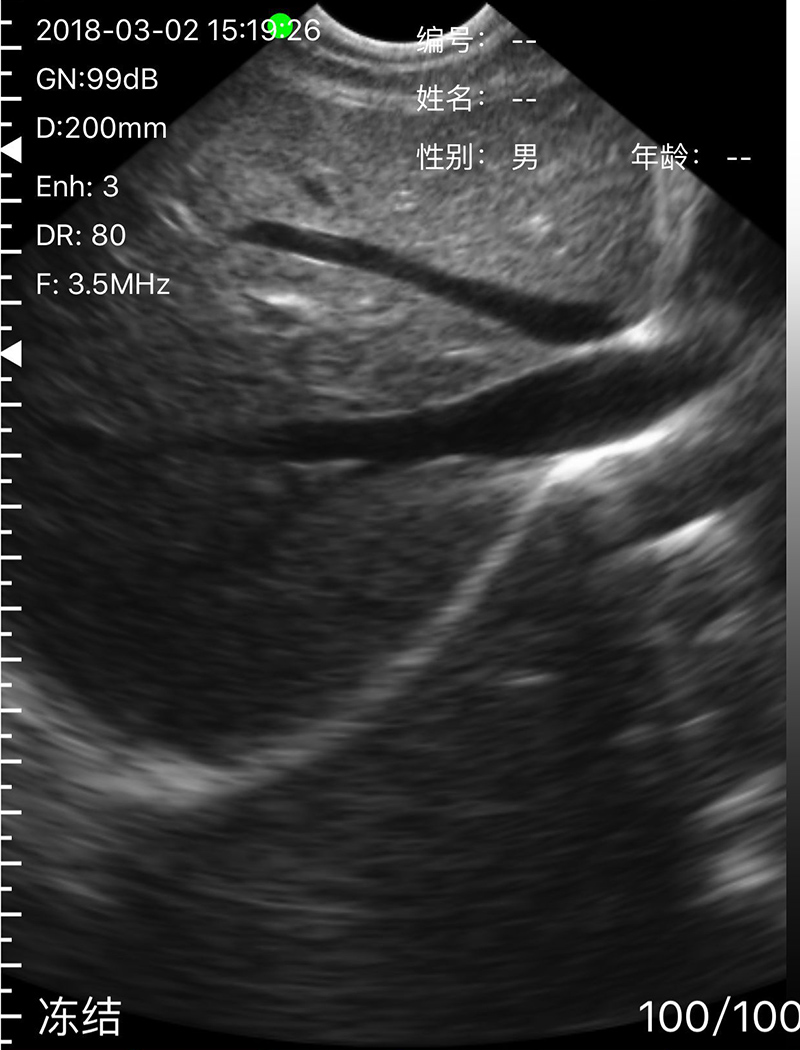

• Scan mode: Electronic Array, convex with cardiac namely phased array or linear array scanning;

• Frequency: Micro-Convex probe 5.0/7.0MHz, Linear probe 10/12MHz

• Scanning Depth: Micro-Convex 60-160mm, Linear 20-80mm, adjustable

• Display mode: B, B/M, Color, PDI, PW